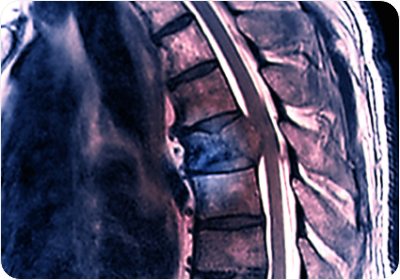

외부충격이나 노화로 인해 발생!

주로 교통사고와 같은 큰 외부 충격이나 노화로 인한 퇴행성 변화, 수술 후 합병증 등에 의해 발생하는데, 큰 통증이 동반되며 근력이 떨어지는 것이 특징!

척추전방전위증의 원인

노화로 인한 퇴행성 변화 -

바르지 못한 자세습관 및 운동 부족 -

교통사고, 낙상 등의 외상으로 인함 -

선천적인 원인 -

허리에 무리를 주는 잘못된 생활습관 -

척추 종양 및 감염 등 외부 요인